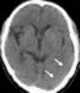

Cerebral infarction

A cerebral infarction is an area of necrotic tissue in the brain resulting from a blockage or narrowing in the arteries supplying blood and oxygen to the brain. The restricted oxygen due to the restricted blood supply causes an ischemic stroke that can result in an infarction if the blood flow is not restored within a relatively short period of time. [Source: Wikipedia ]